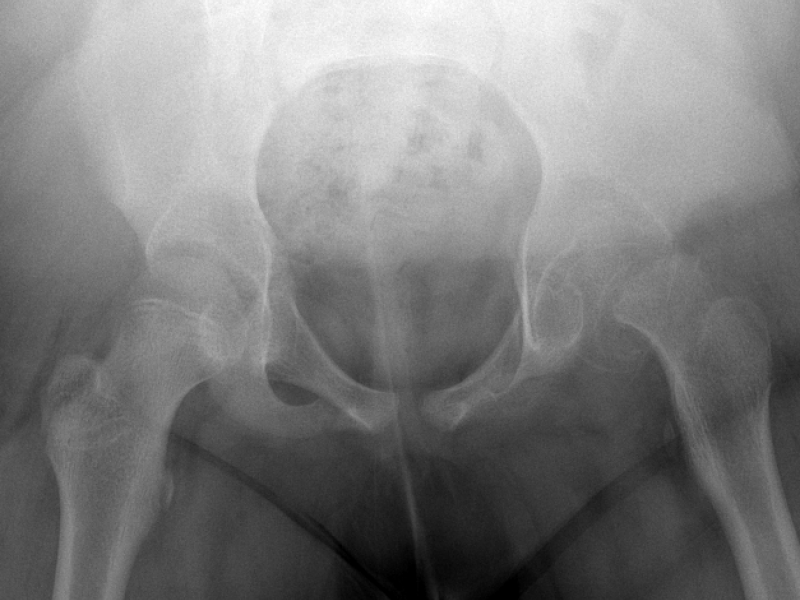

8 yo F presents to the ED c/o L hip pain. Reports fall 1